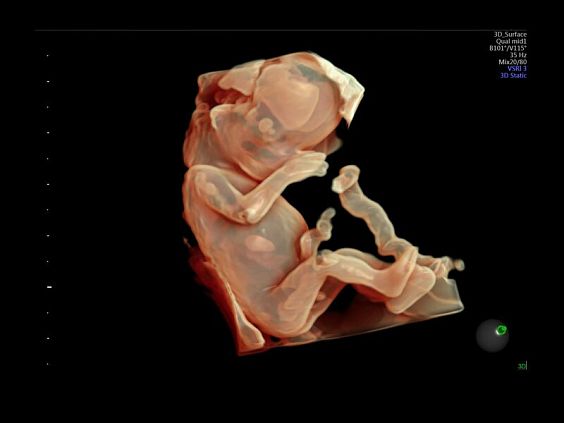

• Программа объемной визуализации плода классический HD-Live + расширенный пакет Hdlive Silhouette и Studio:

• HDlive Studio - три независимых источника освещения с регулировкой интенсивности

• Автоматическое определение плода в режиме 3D (SonoRenderLive) – позволяет значительно экономить время и получать изображение конечностей и лица плода в режимах 3D без артефактов и помех – система автоматически определяет границы конечностей и лица плода и выстраивает объемное изображение

Инновационная технология визуализации HDlive обеспечивает получение реалистических изображений за счет эффекта объемного зрения, повышая достоверность клинической оценки. Теперь режим HDlive дополняют две новые функции: